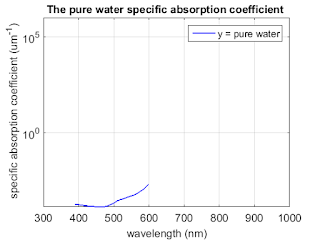

Matlab code to compute the corresponding absorption coefficients

% Matlab code to compute the corresponding absorption coefficients and plot

% the three absorption spectra on the same graph.

% Identify the low-absorption near-IR window that provide deep

% penetration.

% data for molar extinction coefficients of oxy-and deoxyhemoglobin and

% absorption coefficient of pure water as a function of wavelength are

% copied directly from this website: http://omlc.org/spectra/hemoglobin/summary.html

%% purewater

load ('purewater.mat');

figure;

semilogy(water(:,1), water(:,2), 'b', 'linewidth',1.5);

title('The pure water specific absorption coefficient ','FontSize',14);

set(gca,'FontSize',14);

ylabel(' specific absorption coefficient (um^{-1})','fontsize',14);

xlabel('wavelength (nm)','fontsize',14);

axis([300 1000 0 1*10^6]);

set(gcf,'PaperUnits','inches','PaperPosition',[0 0 6 5]);

grid on;

legend('y = pure water')